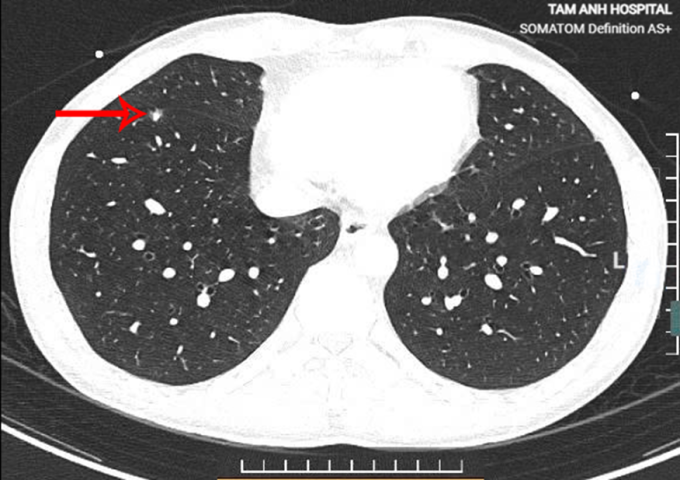

TS.BS Vũ Hữu Khiêm, Trưởng khoa Ung bướu, cho biết sau hai năm, nốt phổi của anh Thắng tiến triển từ nguy cơ thấp lên nguy cơ cao nhất (4X) trên thang xếp độ LungRADS. Nốt thùy dưới phổi có phần đặc, kích thước 4,5×7,6 mm, bờ tua gai, co kéo nhẹ màng phổi rãnh liên thùy.

Nốt phổi nguy cơ cao của anh Thắng trên phim chụp CT liều thấp. Ảnh: Bệnh viện Đa khoa Tâm Anh